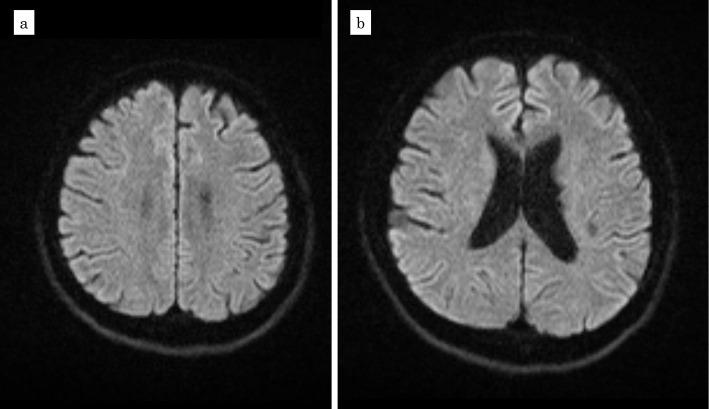

A 40-year-old man was admitted to the hospital due to both a worsening of symptoms associated with ulcerative colitis (UC), which had been diagnosed 3 years previously, and limb paralysis. Colonoscopy revealed severe pancolitis-type UC. He was diagnosed with cerebral vasculitis with multiple white matter infarctions associated with the disease activity of UC by contrast-enhanced head magnetic resonance imaging. Mesalazine at 4,000 mg/day and prednisolone at 60 mg/day were started, and the prednisolone dosage was thereafter gradually reduced and switched to golimumab. He achieved a long-term remission from UC, and thereafter his neurological abnormalities improved significantly. He had no recurrence of cerebral infarction.

一位 40 岁男性因溃疡性结肠炎(UC)相关症状恶化和肢体瘫痪而入院,该患者 3 年前被诊断为 UC。结肠镜检查显示严重的全结肠炎型 UC。对比增强头部磁共振成像显示,患者患有脑血管炎,伴有多发性脑白质梗死,与 UC 的疾病活动有关。给予患者美沙拉嗪 4000mg/天和泼尼松龙 60mg/天治疗,此后逐渐减少泼尼松龙剂量并换用戈利木单抗。患者 UC 达到长期缓解,此后神经功能异常显著改善。他没有再次发生脑梗死。